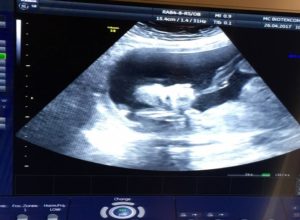

Una semana después la próxima visita a la clínica. El primer ultrasonido y ambos pudieron conocer a una madre sustituta que debería dar a luz a su hijo. Fueron llevados a la habitación. Detrás de la pared en el estilo español yacía Svetlana, su madre subrogada. Las imágenes de ultrasonido se transfirieron a una pantalla plana, y las paredes delante de las cuales eran sillas, como en un cine. “Entonces te das cuenta por primera vez: Aquí está, hijo mío. Inmediatamente comencé a llorar. Un momento tan conmovedor, aunque un poco extraño. Melanie trajo regalos para Svetlana y su familia. Svetlana tiene 33 años, es madre de tres hijos y no habla el alemán ni el inglés. Pero esto no era necesario. Cuando salió por detrás de la división, las dos mujeres inmediatamente se abrazaron.